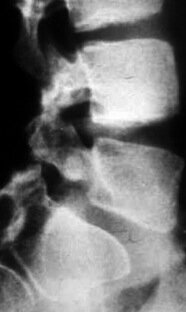

La Spondilolistesi